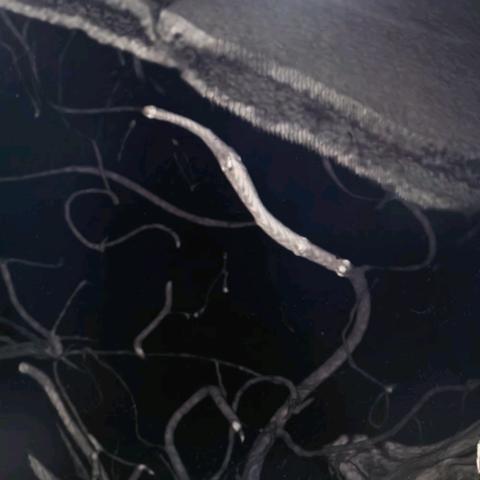

徐建国,男,45岁,额叶动静脉畸形-动静脉入路

01-26 264阅读